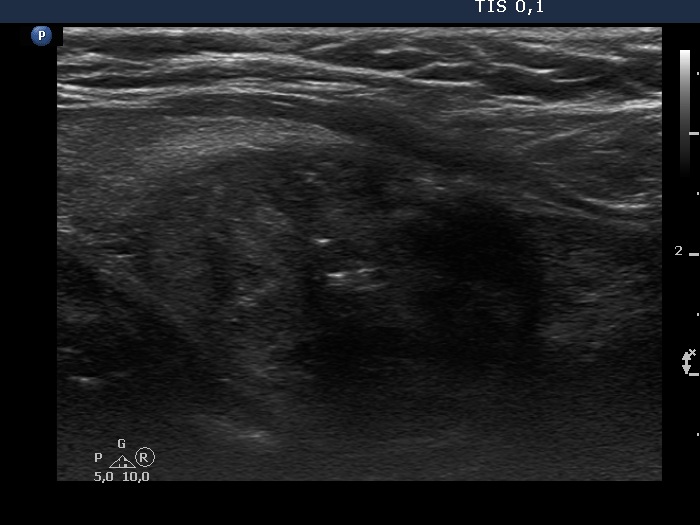

Benign colloid goiter (cytological diagnosis) - case 1429

The nodule has pale hyperechogenic granules and lines corresponding to the normal architecture of the thyroid consisted of connective tissue.